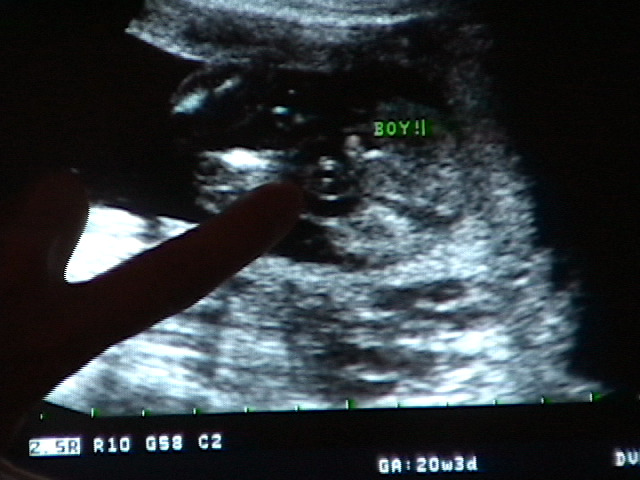

5. It's a Boy!!

• 2009-12-07

• Dave Allen Barker Jr

We got a sonogram today, and we have a boy on the way!

[Photo] Exciting!

[Sonogram] Boy!